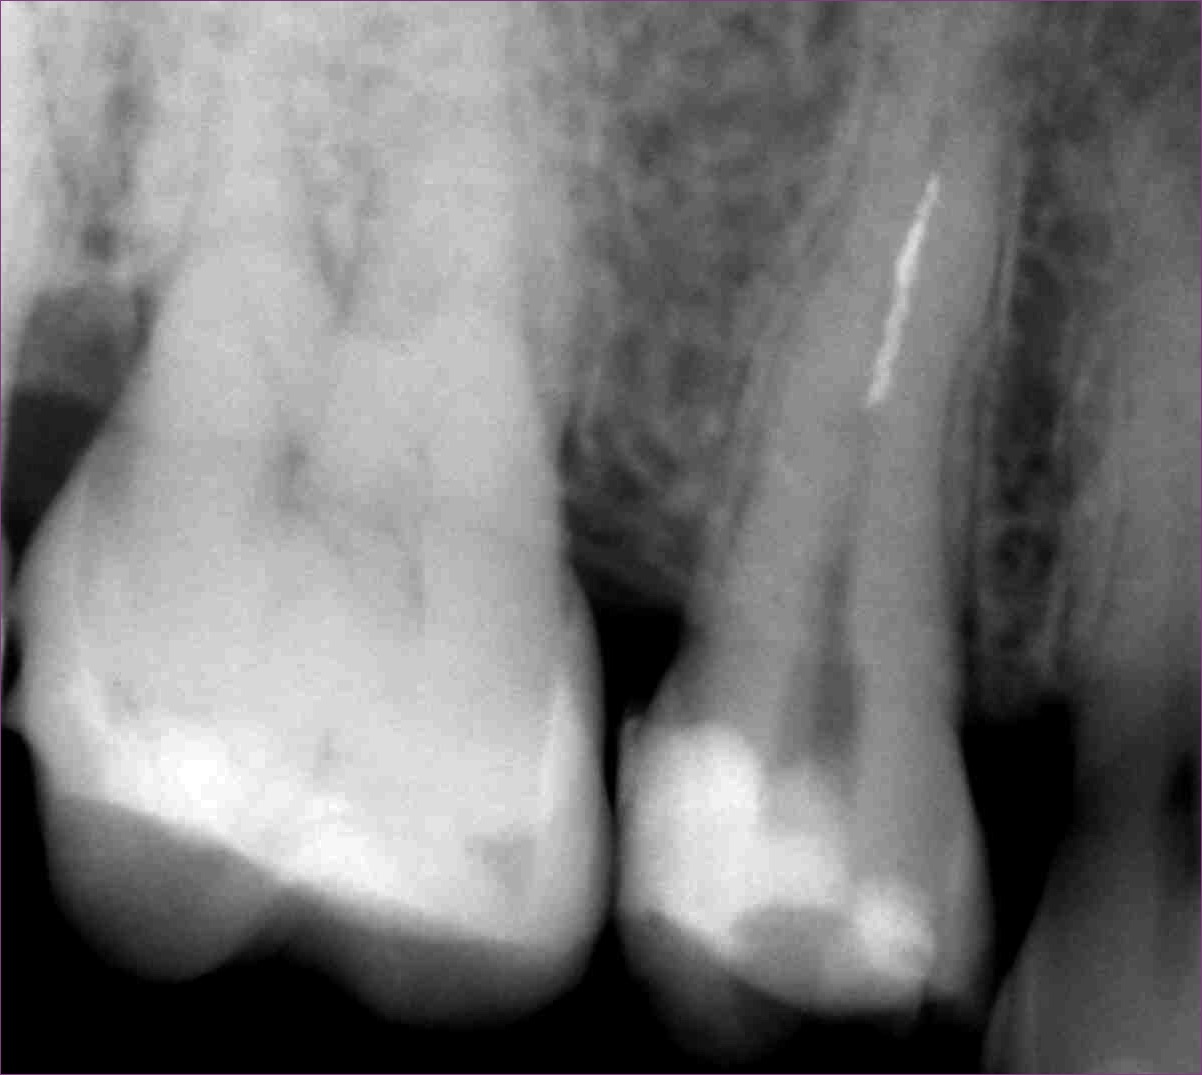

Mivel az eddig kezelt csatornában gond nélkül végig tudtunk haladni, egyértelmű volt, hogy a másik darabka a másik csatornában található. Kis kutakodás után ezt is sikeresen megtaláltuk, és eltávolítottuk. Ezt igazolandó készült egy újabb kontrollröntgen. Az eddig leírt kezelések összesen két alkalmat vettek igénybe, hiszen ez egy időigényes, precíz beavatkozás, hogy a lehető legtöbb saját foganyagot tartsuk meg kezelés közben.

mikroszkópos gyökérkezeléssel megmentett fog: a bent rekedt fragmentumok eltávolítása 3